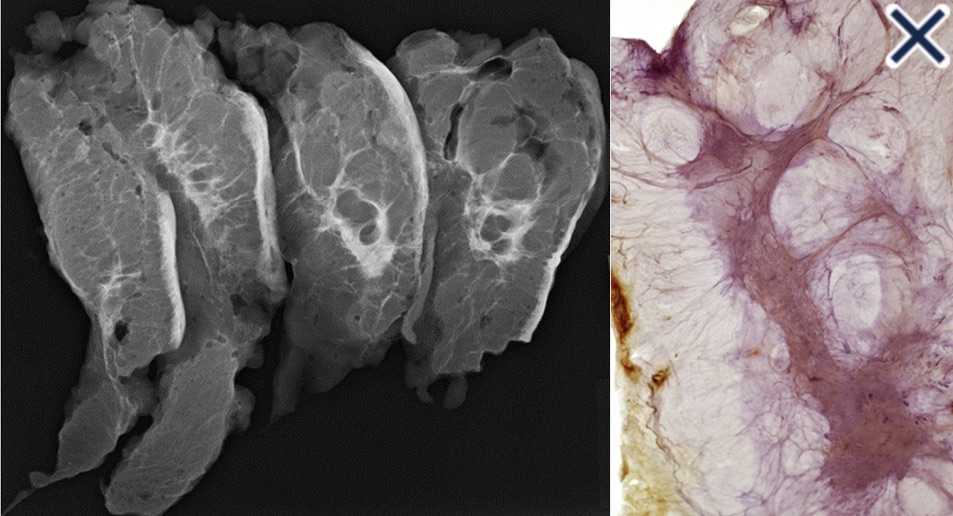

- The subgross (3D) histopathology images:

- Show how growth of the mesenchymal tissue distorts the normal, harmonious connective tissue framework by causing nonuniform thickening of the fine sheets of connective tissue (Images 3a -b)

- The growth pattern and cell type of diffusely invasive breast cancer:

- Is very similar to that of diffuse gastric carcinoma (linitis plastica):

- Both of these diseases can be associated with a deleterious mutation in the CDH1 gene:

- Which is located on chromosome 16q22:

- It codes for e-cadherin protein (Image 5a, Image 5b)